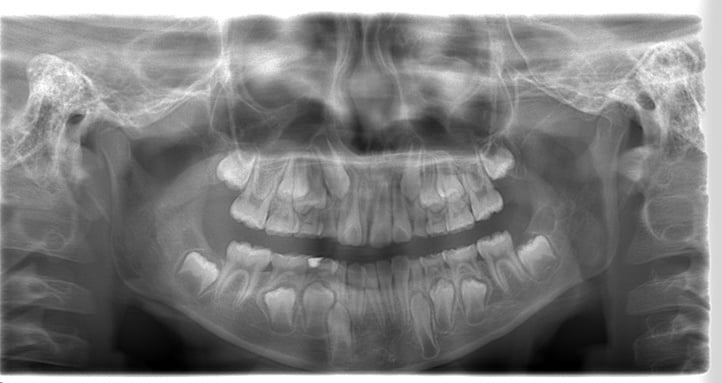

パノラマ(お口全体のレントゲン)・セファロ(お顔・手のレントゲン)・口腔内写真(現在の歯並びの写真)・顔写真・歯の型取り

をして丁寧に状態の確認を行います。

パノラマ

歯や骨、顎関節の状態などさまざまな情報を得ることができます。